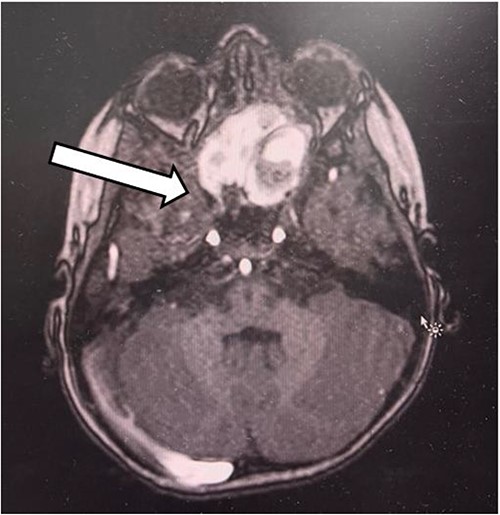

In the operating room (OR), examination under general anesthesia (GA) using a rigid nasal endoscope showed a heterogenous mass in the posterior nasal septum destructing the vomer, rostrum, and sphenoid wing. The mass was evacuated by the EEA while using the navigation system. The evacuation extended posteriorly to the sphenoid sinus, laterally to the sphenoid wing, and superiorly to the skull base (Figs 3 and 4). Lastly, Doyle nasal splints were inserted bilaterally to prevent re-accumulation of a hematoma (Fig. 5). Post-operatively, NovoSeven was administered for optimization. The patient was discharged in stable condition, and 10 days later underwent removal of the splints in the OR under GA. He followed up post-operatively at the otolaryngology clinic and was doing well, with no further complaints of epistaxis.